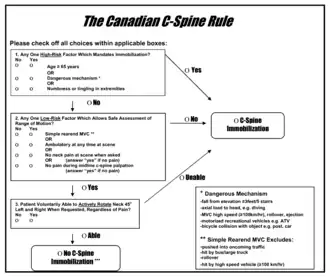

There are two main algorithms, the Canadian C-spine rule and NEXUS, which are used to decide who requires cervical spine imaging via CT scan[6] after blunt trauma, and who can be cleared without imaging.[4] The Canadian C-spine rule appears to have greater sensitivity and specificity (i.e. fewer false positives and false negatives).[17] However, following either rule is reasonable.

If the chosen decision rule (NEXUS or Canadian C-spine) is negative, or if cervical spine imaging is negative, the cervical collar can be removed if the patient does not have significant midline tenderness and can move the neck 45 degrees to both sides.[6] If a patient cannot do both, the collar should be replaced and additional imaging or follow-up should be pursued depending on facility guidelines.[6]